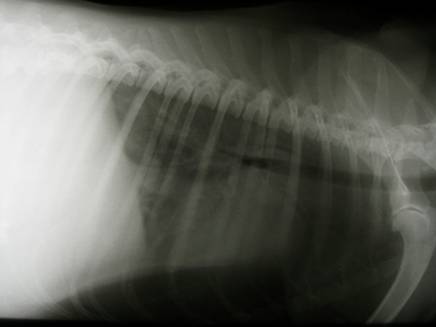

Ebenfalls einen Herzbeutel-Erguss zeigte „WILLI“, ein Kater mit 15 Jahren, als er nach dem Auftreten von Schwäche und „Hecheln wie ein Hund“ von einer Klinik überwiesen wurde. Aufgrund mangelnder Kooperation wurde „Willi“ nach der Sono-Diagnose schlafen gelegt um 25 ml einer relativ klaren Flüssigkeit abzusaugen. |

Röntgen: |

Flüssigkeitsansammlung im Thorax (rote Pfeile) und vergrößerte Herzsilhouette |